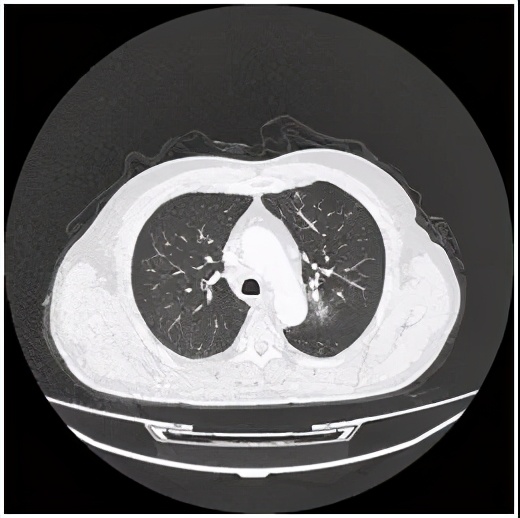

右肺肿瘤消失